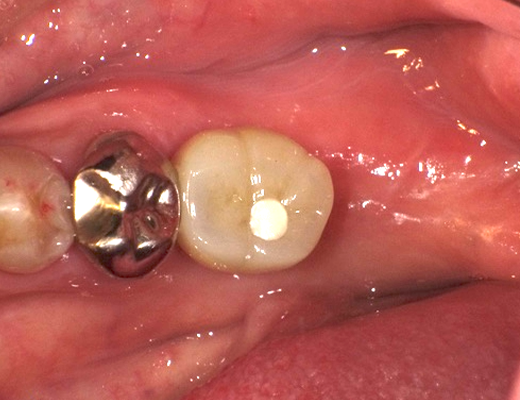

当院ではインプラントの手術前に必ずCT撮影を行い、骨の状態や重要な神経の位置の精査をします。この精密検査を行うことによりインプラントの埋める方向や深さの安全性を事前に確認することができます。

実際の手術を行う際にはサージカルガイドを用いることにより、事前に計画したインプラントの埋める方向や深さと誤差が無い正確な手術を行っております。

インプラントはノーベルバイオケア社製の製品を使用しています。ノーベルバイオケア社は今のインプラントの原型を開発したメーカであり約40年の実績があります。